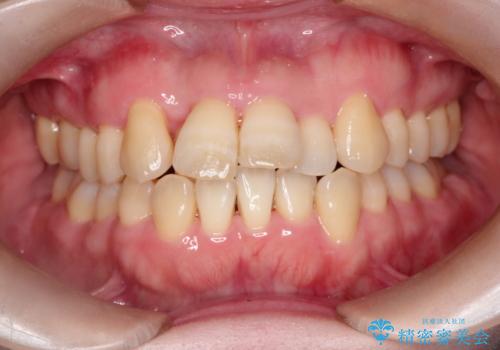

【インビザライン】ずれた前歯の噛み合わせをなおしたい

- 前歯の噛み合わせが悪いことを主訴に来院されました。

歯周病も併発していたため、歯牙への負担が少なくなるように治療計画をたて、インビザラインにて治療を完了しました。

矯正開始前に半年間、歯周治療を行ってからインビザラインを装着しています。